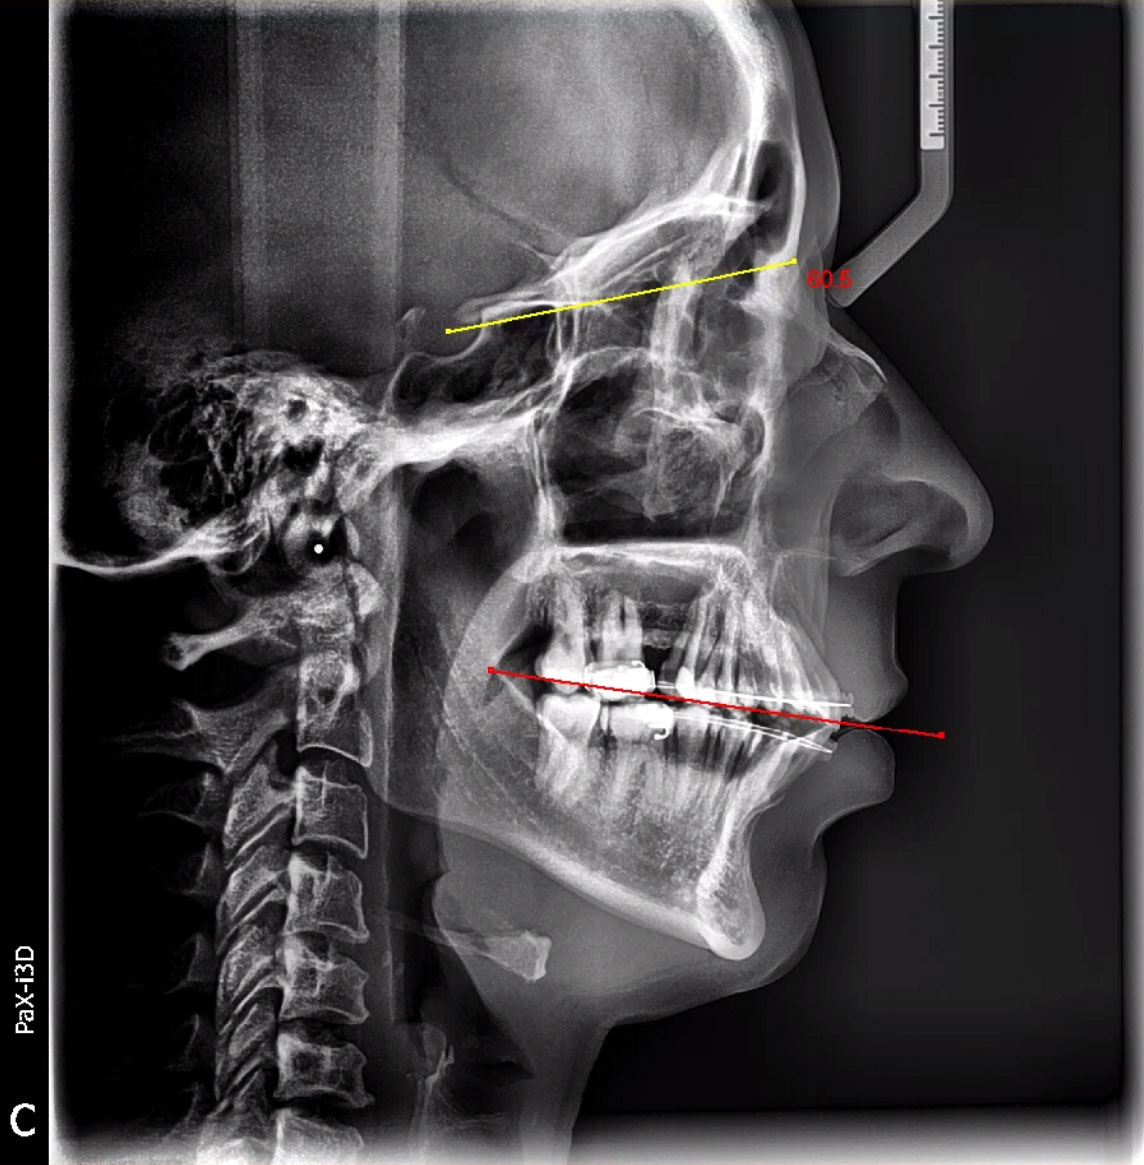

En Radiología Dental les ofrecemos estudios radiológicos dentales con la tecnología digital 3D más avanzada del mercado, facilitándoles imágenes con una gran riqueza de detalles y una nitidez extraordinaria.